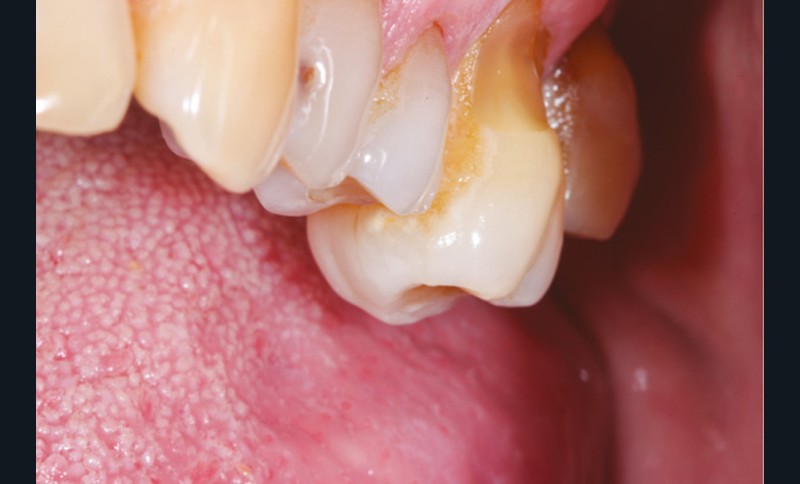

Cette version, quand elle se produit, modifie les espaces interdentaires et complique l’hygiène proximale des patients. Des caries peuvent alors se développer en interproximal sans que cela soit forcément visible à l’examen visuel (fig. 3 et 4). Les radios de type bite-wing (rétro-coronaires) prennent alors tout leur sens (fig. 5 et 6).